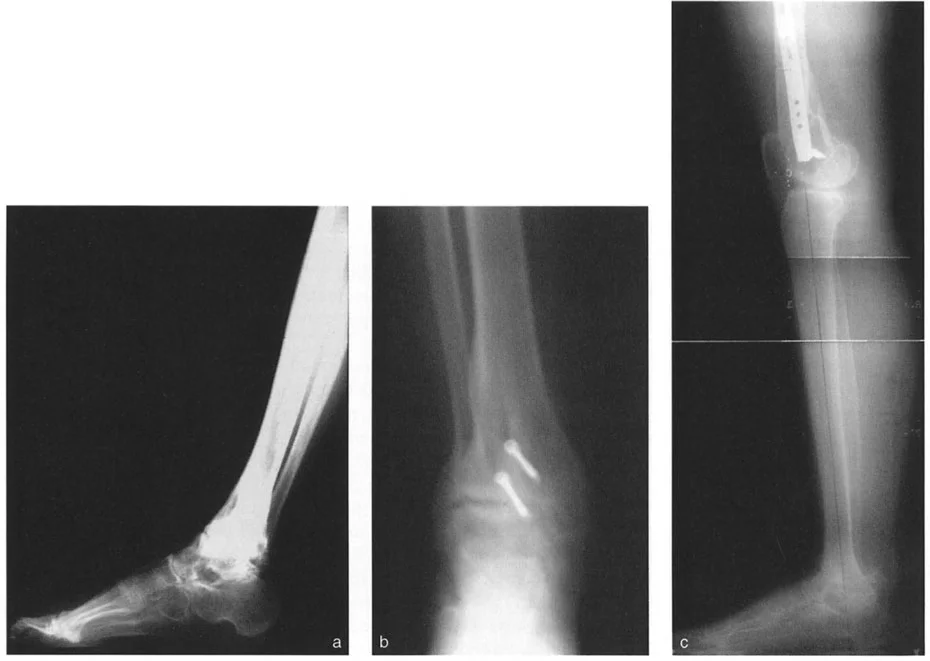

* نقص تنسج الشظية (Fibular Hemimelia): وهي حالة يولد فيها الطفل بشظية (عظم الساق الأصغر) أقصر من الطبيعي أو مفقودة جزئيًا. هذا يؤثر بشكل كبير على نمو قصبة الساق والكاحل، مما يؤدي إلى تشوهات شديدة في المحاذاة منذ الولادة. في هذه الحالات، يكون مركز دوران التشوه (CORA) عادةً عند مستوى المفصل نفسه.

* الكسور غير الملتئمة أو الملتئمة بشكل خاطئ: إذا لم يتم علاج كسر في الجزء السفلي من قصبة الساق أو الكاحل بشكل صحيح، أو إذا حدث التئام للعظم في وضع غير طبيعي، فقد يؤدي ذلك إلى تشوه دائم. على سبيل المثال، كسر في الكاحل يلتئم مع تقوس (Varus) أو روحبة (Valgus) في قصبة الساق يمكن أن يغير ميكانيكا الكاحل بشكل جذري.

جراحة قطع العظم فوق الكاحل (SMO) هي الإجراء الأكثر شيوعًا لتصحيح تشوهات قصبة الساق البعيدة. تتضمن هذه الجراحة قطعًا دقيقًا في عظم الساق (القصبة) فوق مفصل الكاحل مباشرة، ثم إعادة محاذاة العظم وتثبيته في الوضع الصحيح. هناك عدة أنواع من هذه الجراحة:

1. قطع العظم الإسفيني الفاتح (Opening Wedge Osteotomy):

• يتم عمل قطع في العظم ثم فتح فجوة صغيرة فيه. تُملأ هذه الفجوة عادةً بترقيع عظمي (من جسم المريض أو من متبرع).

2. قطع العظم الإسفيني المغلق (Closing Wedge Osteotomy):

• يتم إزالة قطعة صغيرة من العظم على شكل إسفين، ثم يتم تقريب أطراف العظم وربطها معًا.

• المميزات: يوفر استقرارًا عاليًا، ويسمح بالاتصال المباشر بين العظام، مما يسرع الالتئام ويسمح غالبًا بتحميل الوزن مبكرًا.